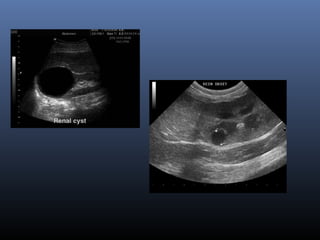

Kyste renal

(renal cyst)

 U lành tính, ch a đ n thu n là d chứ ơ ầ ị

Siêu âm

 T n th ng tròn , echo tr ng đ ng nh t, vổ ươ ố ồ ấ ỏ

r t m ngấ ỏ

 V trí: v , c nh bê th nị ỏ ạ ậ

Nang xuất huyết

Nang xuất huyết nhiễm trùng